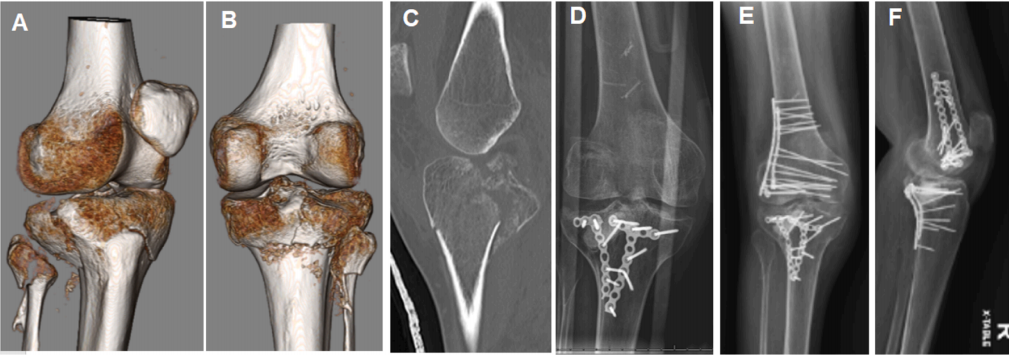

A-C) CT 扫描图像显示 43 岁男性后侧、后外侧和前内侧平台骨折。 D) 34 个月随访 X 光片(因新发症状拍摄),显示股骨远端外侧髁骨折,同时显示胫骨平台骨折愈合(位置与初次 ORIF 后相比无变化)且植入物稳定。 F, G) 使用两块外侧微型钢板进行股骨远端骨折 ORIF 术后 3 个月拍摄的 X 光片,显示股骨髁骨折愈合且所有植入物稳定。